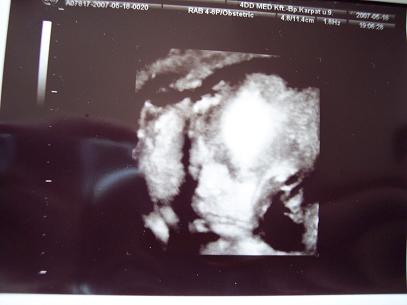

Jucu és a "hasa" :-)

íme a "has" :-) 26 hetes picurunk

Ma megyek 4D re ,kivi vagyok mekkorára növesztettem a kicsifiam.Ha kicsifiú egyáltalán :wink: :lol:

Kép pofikánk